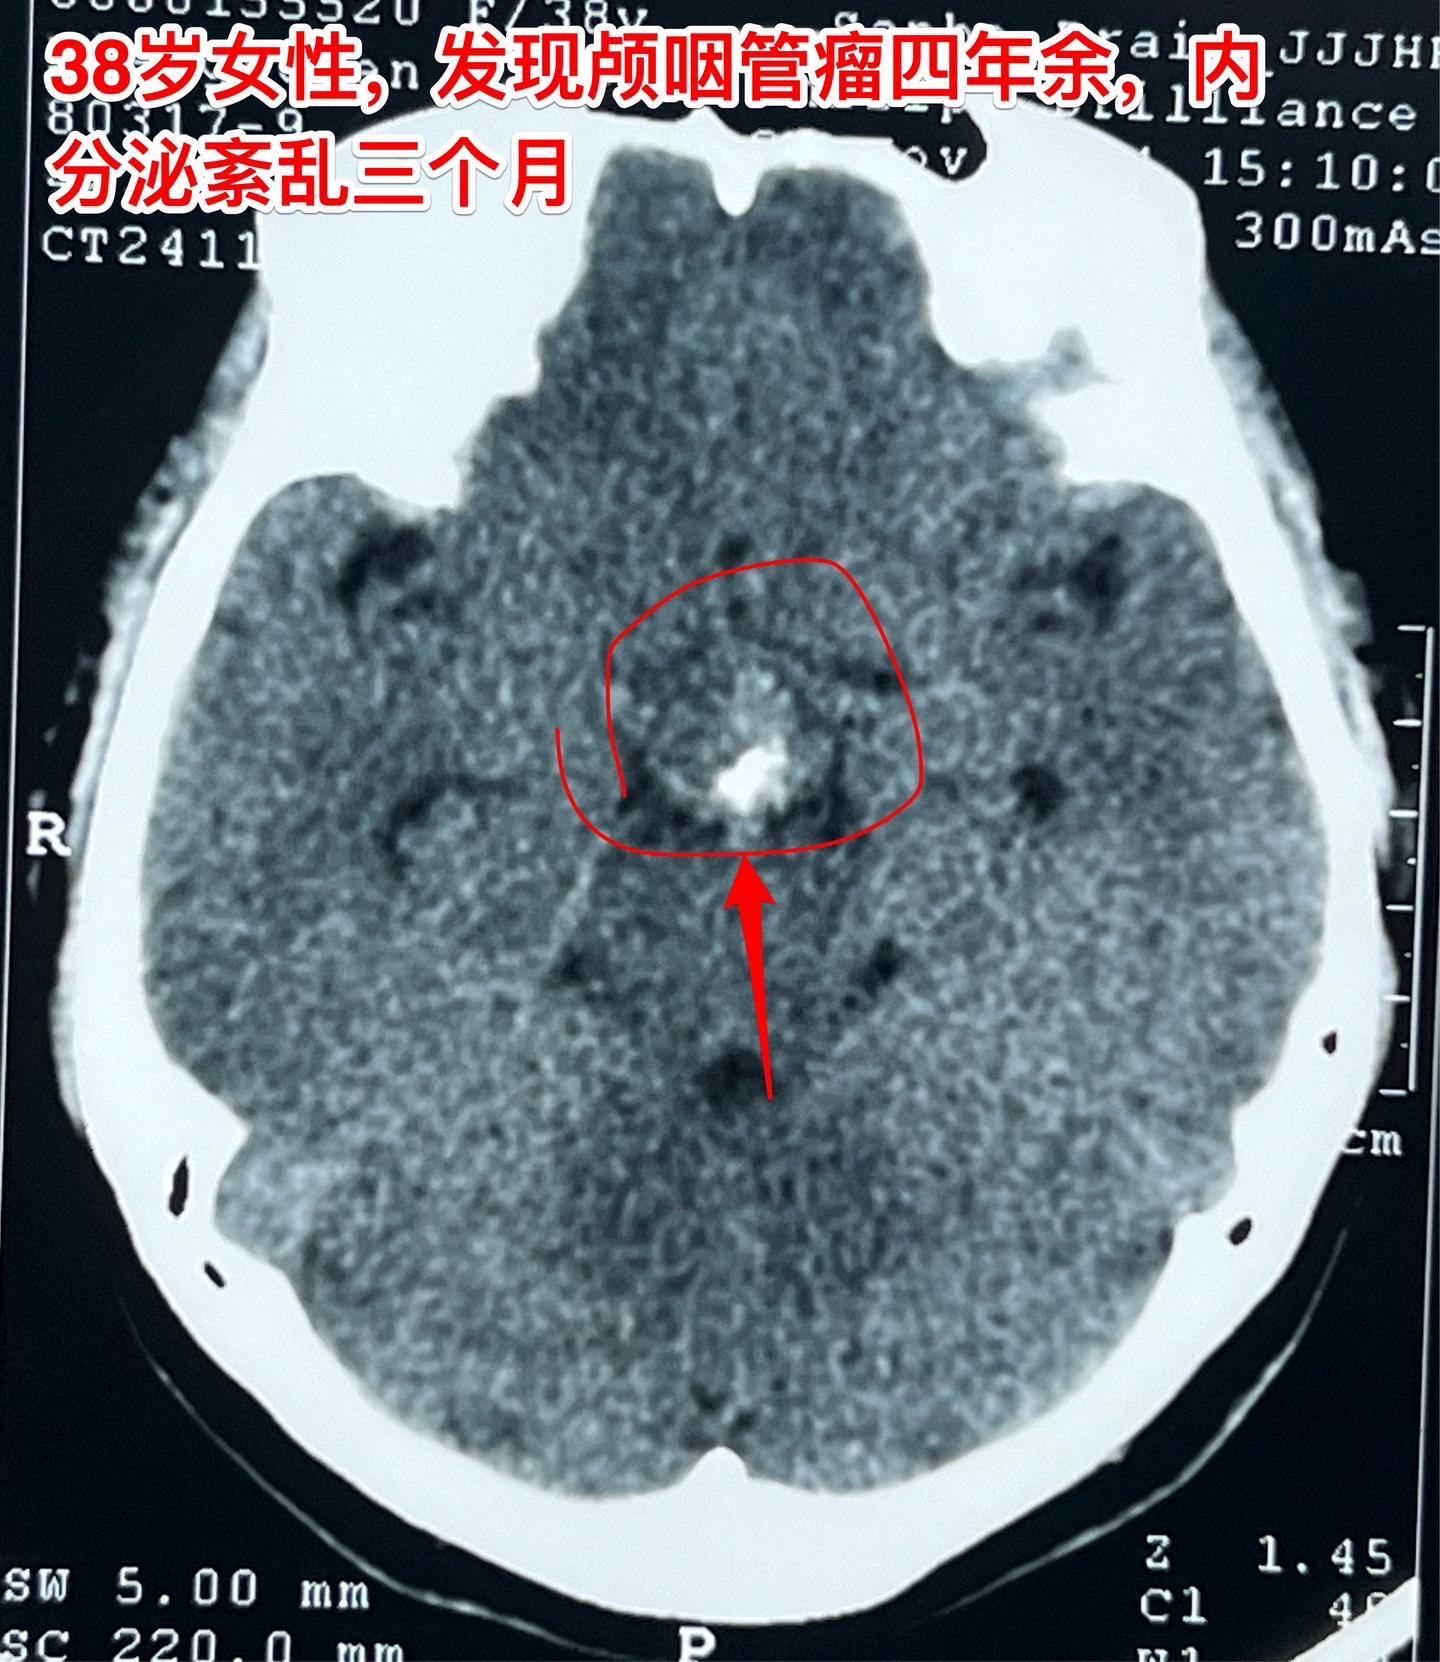

颅咽管瘤等待四年多才作手术,是否合适?偶然发现的颅咽管瘤,病人几乎没有什么症状,是不是要尽早作手术呢?颅咽管瘤的治疗一直是神经外科界的难题,手术时机选择也是一个难点。 今天以一个实际的病人来说明。 38岁的绍兴女性,在2020年初经体检发现了颅咽管瘤,当时几乎没有什么症状,曾经通过咨询过我,之后一直在观察。患者在2014年左右生育孩子,发现颅咽管瘤后内分泌系统都很正常。 直到今年夏天患者发现内分泌系统紊乱了,复查磁共振显示肿瘤体积增大了。她这才下定决心找我